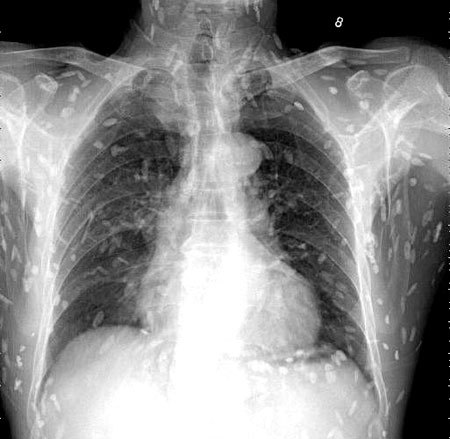

광둥성 푸산시 순더 지역에서 한 남성은 회를 섭취한 뒤, 복부 통증과 피부 가려움증 증상을 겪었습니다. 이로 인해 그는 난팡 의과대학 부속병원을 찾아 진료를 받았습니다. 의사는 이 환자의 증상을 확인하기 위해 엑스레이를 촬영하였고, 이 사진에서는 그의 온몸에 기생충이 퍼져 있는 것을 확인할 수 있었습니다. 이러한 기생충은 촌충 또는 열두 조충이라고 불리는 벌레로서, 사람의 장내에서 기생하는 것으로 알려져 있습니다.